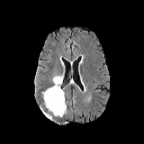

Brats MRI T1 Scans, FLAIR, Tumors. Lastly, we used a dataset of brain MRI scans [28] with two modalities: T1 (naive) and FLAIR (T2 Fluid Attenuated Inversion Recovery) [15]. We adapt the protocol that Cohen et al. [9] used for the Brats2013 datasets [27] to the more recent Brats2018 [3] dataset by varying the percentage of scans with tumors in the target domain. We selected transverse slices from the to range in the caudocranial direction [1] for both T1 and FLAIR scans. Each scan was classified as tumorous if more than of its pixels were labeled as such, and as healthy if it contained no tumor pixels. The training set contains images from each modality, with all source images (T1) being healthy and the target domain (FLAIR) comprising tumorous scans. The test set contains paired scans of healthy brains.

pFPR and iFPR. In the GoogleMap dataset, highways are always depicted in orange, allowing us to label pixels where all color channels differ by less than units from as highways. In the Brats MRI dataset, we use a pretrained tumor detector [6] to find spurious tumors in the generated images. This allows us to compute the average false positive rate per pixel (pFPR) and per instance (iFPR) of the generated images.

Qualitative Results. Figure 3 showcases StegoGAN’s qualitative performance against other image translation algorithms. Notably, StegoGAN effectively avoids generating unmatchable classes such as texts, highways, and tumors, while producing high-quality image translations.

Quantitative Results. On the PlanIGN dataset (Table 1) and the Brats MRI dataset (Table 2), StegoGAN outperforms others in fidelity, achieving the lowest RMSE by a margin of on PlanIGN and by for Brats MRI. Furthermore, it significantly enhances pixel accuracy, with improvements of in Acc() and in Acc() on PlanIGN. In the MRI dataset, StegoGAN dramatically reduces false positive rates—–over 20 lower than CycleGAN and 10 less than the next best model SRUNIT (for pFPR).

We adapt the protocol of Cohen et al. [9] from the Brats2013 datasets [27] to the more recent, larger, and more diverse Brats2018 dataset [2]. We consider two MRI modalities: native (T1) and Fluid Attenuated Inversion Recovery (FLAIR). We selected transverse slices from the to range in the caudocranial direction [1] for both modalities of scans.

We label each scan as tumorous if more than of its pixels are labelled as such, and as healthy if it contains no tumor pixels. We only use high-grade gliomas (HGG) instead of low-grade gliomas (LGG) as the are more easily observable [24]. In total, we obtain 5035 pathological pairs and 1135 healthy pairs. The train set is composed of a source domain of T1 images of healthy brains, while the target domain set is composed of FLAIR scans of which (60%) are tumorous and healthy. The test set is composed of aligned scans of healthy brains in both modalities.